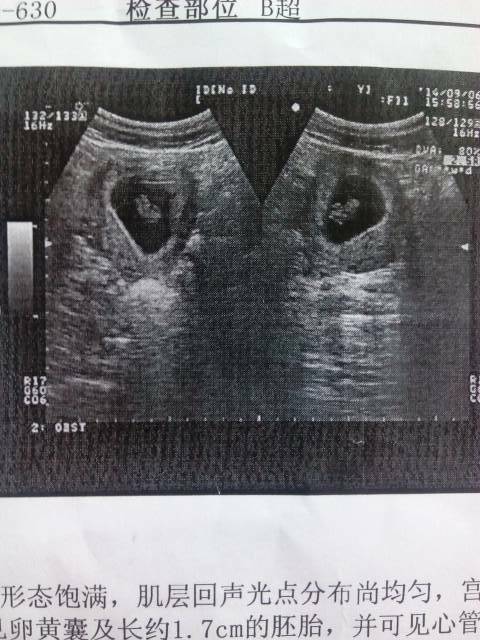

今天去检查了 医生给莪做了B超 说孩子不稳定 还拿黄体酮胶囊和孕康颗粒给莪 孩子的胎位正么?有谁懂

可见心管搏动就说明宝宝发育正常哦,我孕酮低也在吃黄体酮。

宝妈现在没必要担心胎儿的胎位正不正,因为他在子宫里会不断的调整自己的位置,所以宝妈现在没有必要担心胎位。